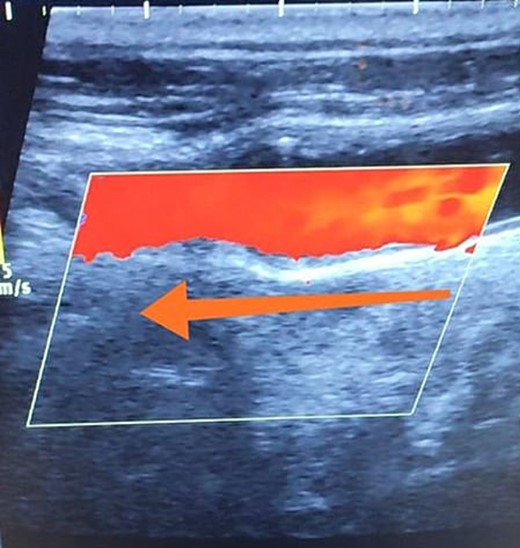

A 65-year-old male presented with recurrent transient ischemic attacks (TIAs), characterized by severe balance disturbances, transient alterations in consciousness, and visual obscurations. Clinical examination revealed high blood pressure in the right arm and absent left radial and brachial artery pulses. Vital signs were normal. Laboratory tests are analyzed as follows: urea: 22 mg/dl, glucose: 150 mg/dl, cholesterol: 199 mg/dl, and triglycerides: 222 mg/dl. A medical history of type 2 diabetes mellitus (DT2), hypertension (HTN), hyperlipidemia, ischemic heart disease, and a heavy smoking history were recorded. Five years before presentation, the patient underwent coronary stenting. Medication history included metformin 1000 mg, aspirin 81 mg, rosuvastatin 40 mg, and ramipril 5 mg. Neck duplex ultrasound (DU) showed normal flow direction and insignificant atherosclerotic plaques in the left internal carotid artery (CA) and left external CA (Figs 1 and 2), normal common CA (Fig. 3), a completely inverted flow direction in the left VA (Fig. 4) that suspected a significant ostial lesion in the left SCA. Multi-slice computed tomography angiography demonstrated 99% stenosis at the left SCA origin and confirmed the presence of SSS (Fig. 5). A balloon angioplasty was unsuccessfully attempted to expand the left SCA. A left carotid VA bypass surgery was performed, and a vascular graft was used to establish a blood flow pathway between the left VA and the left CA. By follow-up, the patient was stable without complications.

Duplex ultrasound showing a completely inverted flow direction in the left vertebral artery.

With a prevalence ranging from 0.6% to 6.4%, SSS is considered a rare phenomenon, and high suspicion is required for diagnosis [2, 5]. The basilar artery is formed by the two vertebral arteries and connects to the brain’s anterior circulation, comprising the Willis circle. However, a steno-occlusive lesion of the proximal SCA may lead to limited blood flow to the upper extremity. Consequently, blood flows through the contralateral VA to the basilar artery, around the circle of Willis, and then descends through the IVA to supply the affected upper extremity, leading to upper limb and vertebrobasilar insufficiency. This altered physiology manifests in signs and symptoms constellation defining SSS [1, 4]. A total of 82.3% of lesions primarily affect the left side as a result of the sharper curvature at the origin of the left SCA, which increases blood flow turbulence and promotes atherosclerotic plaque formation [1, 2, 5–7]. In this case, a patient with retrograde left VA flow on DU is presented (Fig. 4). Most patients are asymptomatic due to developing collateral circulation [2]. However, it may manifest with arterial insufficiency affecting the upper limb (paresthesia, weakness, and claudication), the brain (vertigo, dizziness, diplopia, ataxia, dysarthria, slurred speech, and syncopal episodes) [1, 2, 5, 7], or the heart if the patient has a coronary artery bypass graft supplied by the internal mammary artery [6]. Our patient suffered from recurrent TIA, manifested as severe balance disturbances, transient altered mental status, and amaurosis fugax (transient vision loss). The most common diagnostic tests for SSS are the DU and TDU due to their accessibility and low cost, which show the subsequent retrograde blood flow in the IVA. Additionally, MRA or CT angiography is used as a confirmatory modality [1, 2, 5–8], but the gold-standard is conventional cerebral angiography [1]. A difference in blood pressure readings between arms >20 mmHg is a significant and noticeable sign. In our case, neck DU showed an inverted left VA flow direction (opposite to the carotid) (Fig. 1). MSCT confirmed the diagnosis of SSS, demonstrating a significant ostial lesion in the left SCA. Conservative management is preferred with minimally symptomatic patients by reducing risk factors like a specific regime and treating comorbidities such as: HTN, DT2, hyperlipidemia, and smoking cessation as a part of minimizing morbidity and preventing complications [1, 2, 5–8]. Surgery is recommended for severe and untreated cases through percutaneous intervention or surgical revascularization by using vascular bypass accompanied by angioplasty and stenting [1, 2, 5–7]. In our case, expanding the left subclavian by catheterization did not succeed; however, a left carotid-vertebral bypass was successfully performed. The most common complications are stroke (ranging from 0.4% to 4.7%) due to distal emboli, thrombosis or bleeding and rupture because of aggressive catheter or wire manipulation [1, 7]. In our case, the patient continues on HTN and DT2 medications: ramipril 5 mg, rosuvastatin 40 mg, aspirin 81 mg, and metformin 1000 mg.